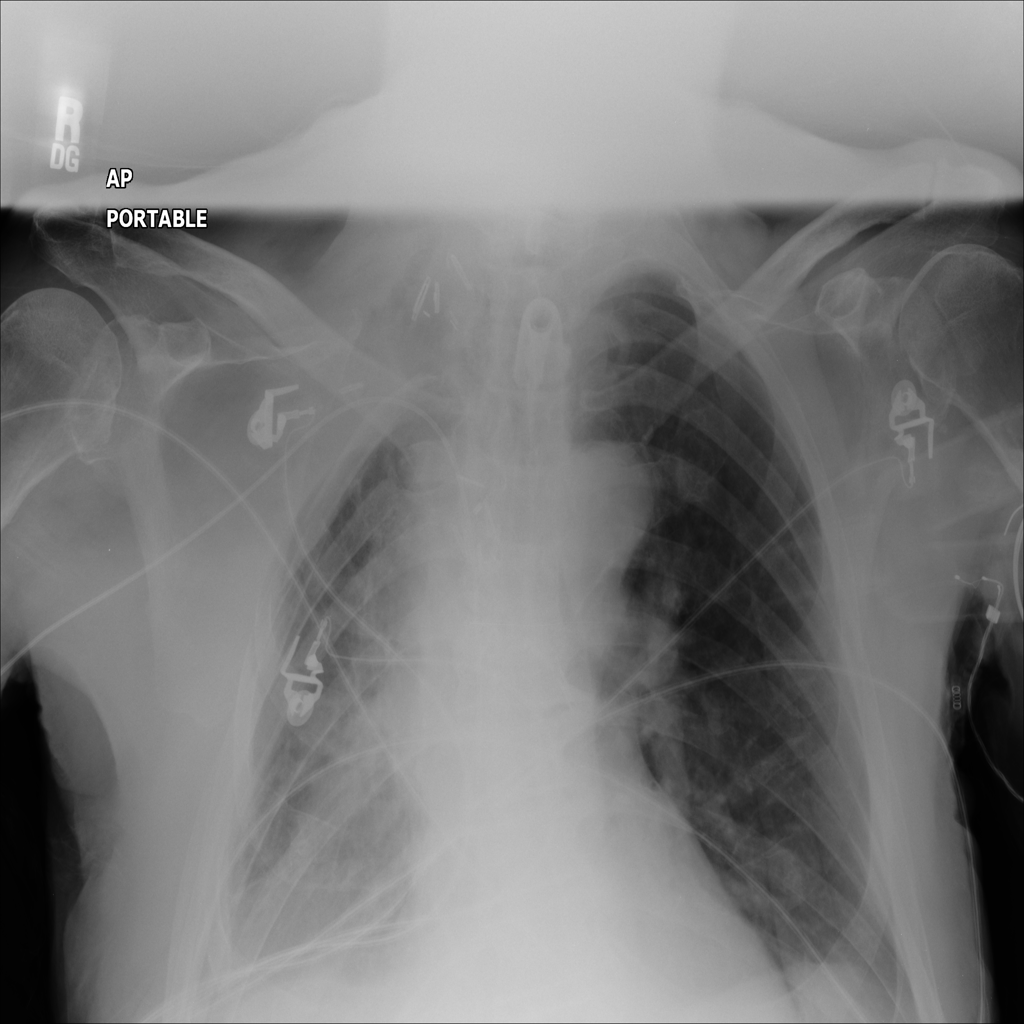

PAT-C0E5 · IMG-001Mass

PAT-C0E5 · IMG-001

PA